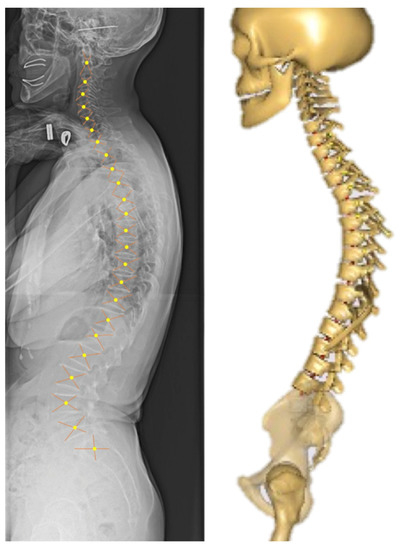

2.2. Image Acquisition and Anatomical Parameters Extraction